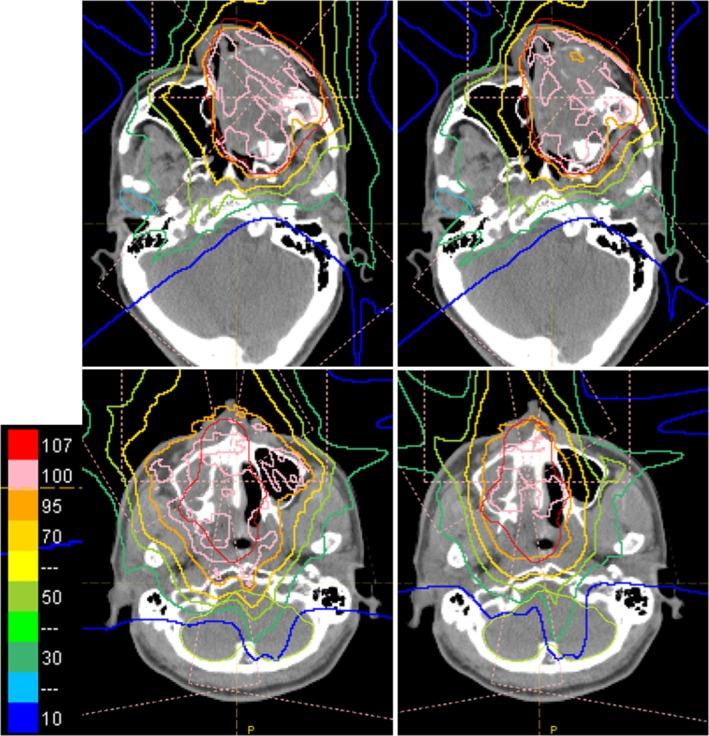

In this study, we evaluate dosimetric advantages of using patient-specific aperture system with intensity-modulated proton therapy (IMPT) for head and neck tumors at the shallow depth. We used four types of patient-specific aperture system (PSAS) to irradiate shallow regions less than 4 g/cm with a sharp lateral penumbra. Ten head and neck IMPT plans with or without aperture were optimized separately with the same 95% prescription dose and same dose constraint for organs at risk (OARs). The plans were compared using dose volume histograms (DVHs), dose distributions, and some dose indexes such as volume receiving 50% of the prescribed dose (V ), mean or maximum dose (D and D ) to the OARs. All examples verified in this study had decreased V and OAR doses. Average, maximum, and minimum relative reductions of V were 15.4%, 38.9%, and 1.0%, respectively. D and D of OARs were decreased by 0.3% to 25.7% and by 1.0% to 46.3%, respectively. The plans with the aperture over more than half of the field showed decreased V or OAR dose by more than 10%. The dosimetric advantage of patient-specific apertures with IMPT was clarified in many cases. The PSAS has some dosimetric advantages for clinical use, and in some cases, it enables to fulfill dose constraints.